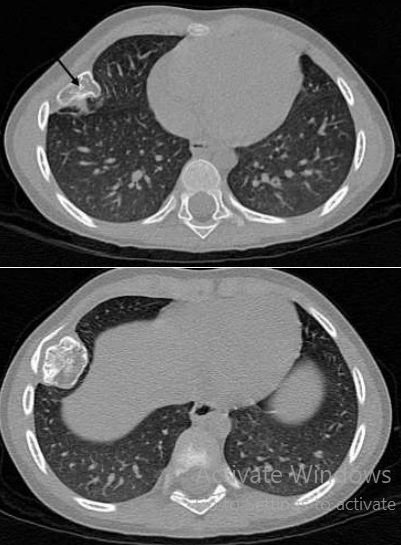

Espect metastatique de

tumefaction de la paroi thoracique droit et de

lyse de destruction osseuse correspondence du

côté droit d'une tumeur metastatique ( fleche rouge

) à origine de cancer pulmonaire ++ droit . Image

radiologique TDM en coupe axial |

|

Image radiologique TDM d'une

tumeur metastatique secondaire de type condensant (

fleche rouge ) de l'arch posterieure du côte

thoracique gauche |

Aspect radiologique de tumeur

metastatique secondaire de type mixte ( lysis et

condensant) multiple disseminé à des côtes du thorax

et à la colonne vertebrale . Image radiologique TDM

en coupe axial , fenêtre mediastinale |